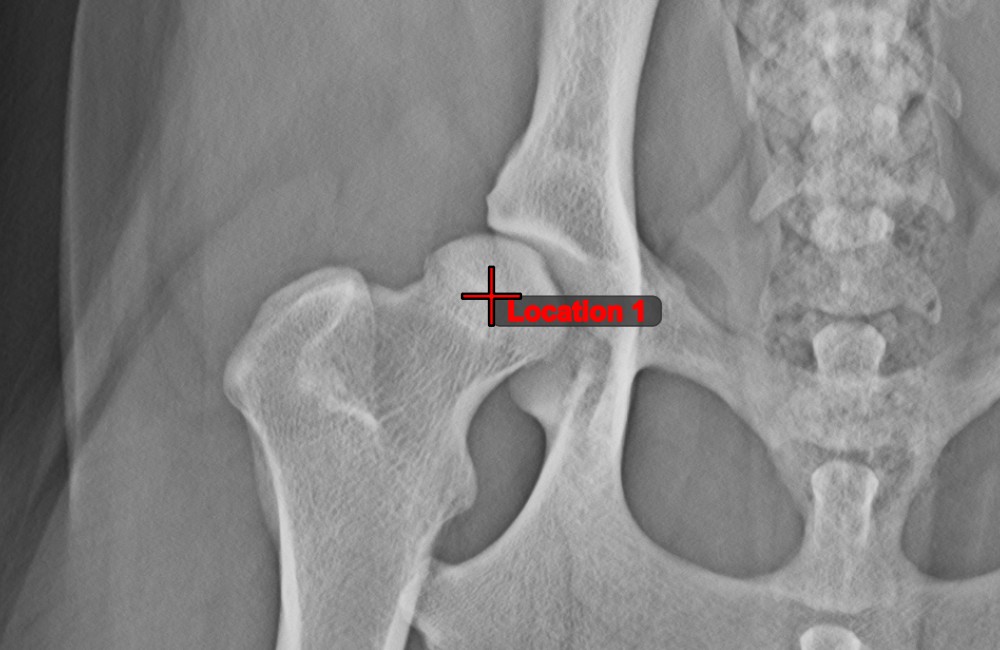

Text Tool¶

Label and comment important information on the image by using the Text Tool

. The text is always assigned to a point that can be later modified by using the Select/Move Item

tool.